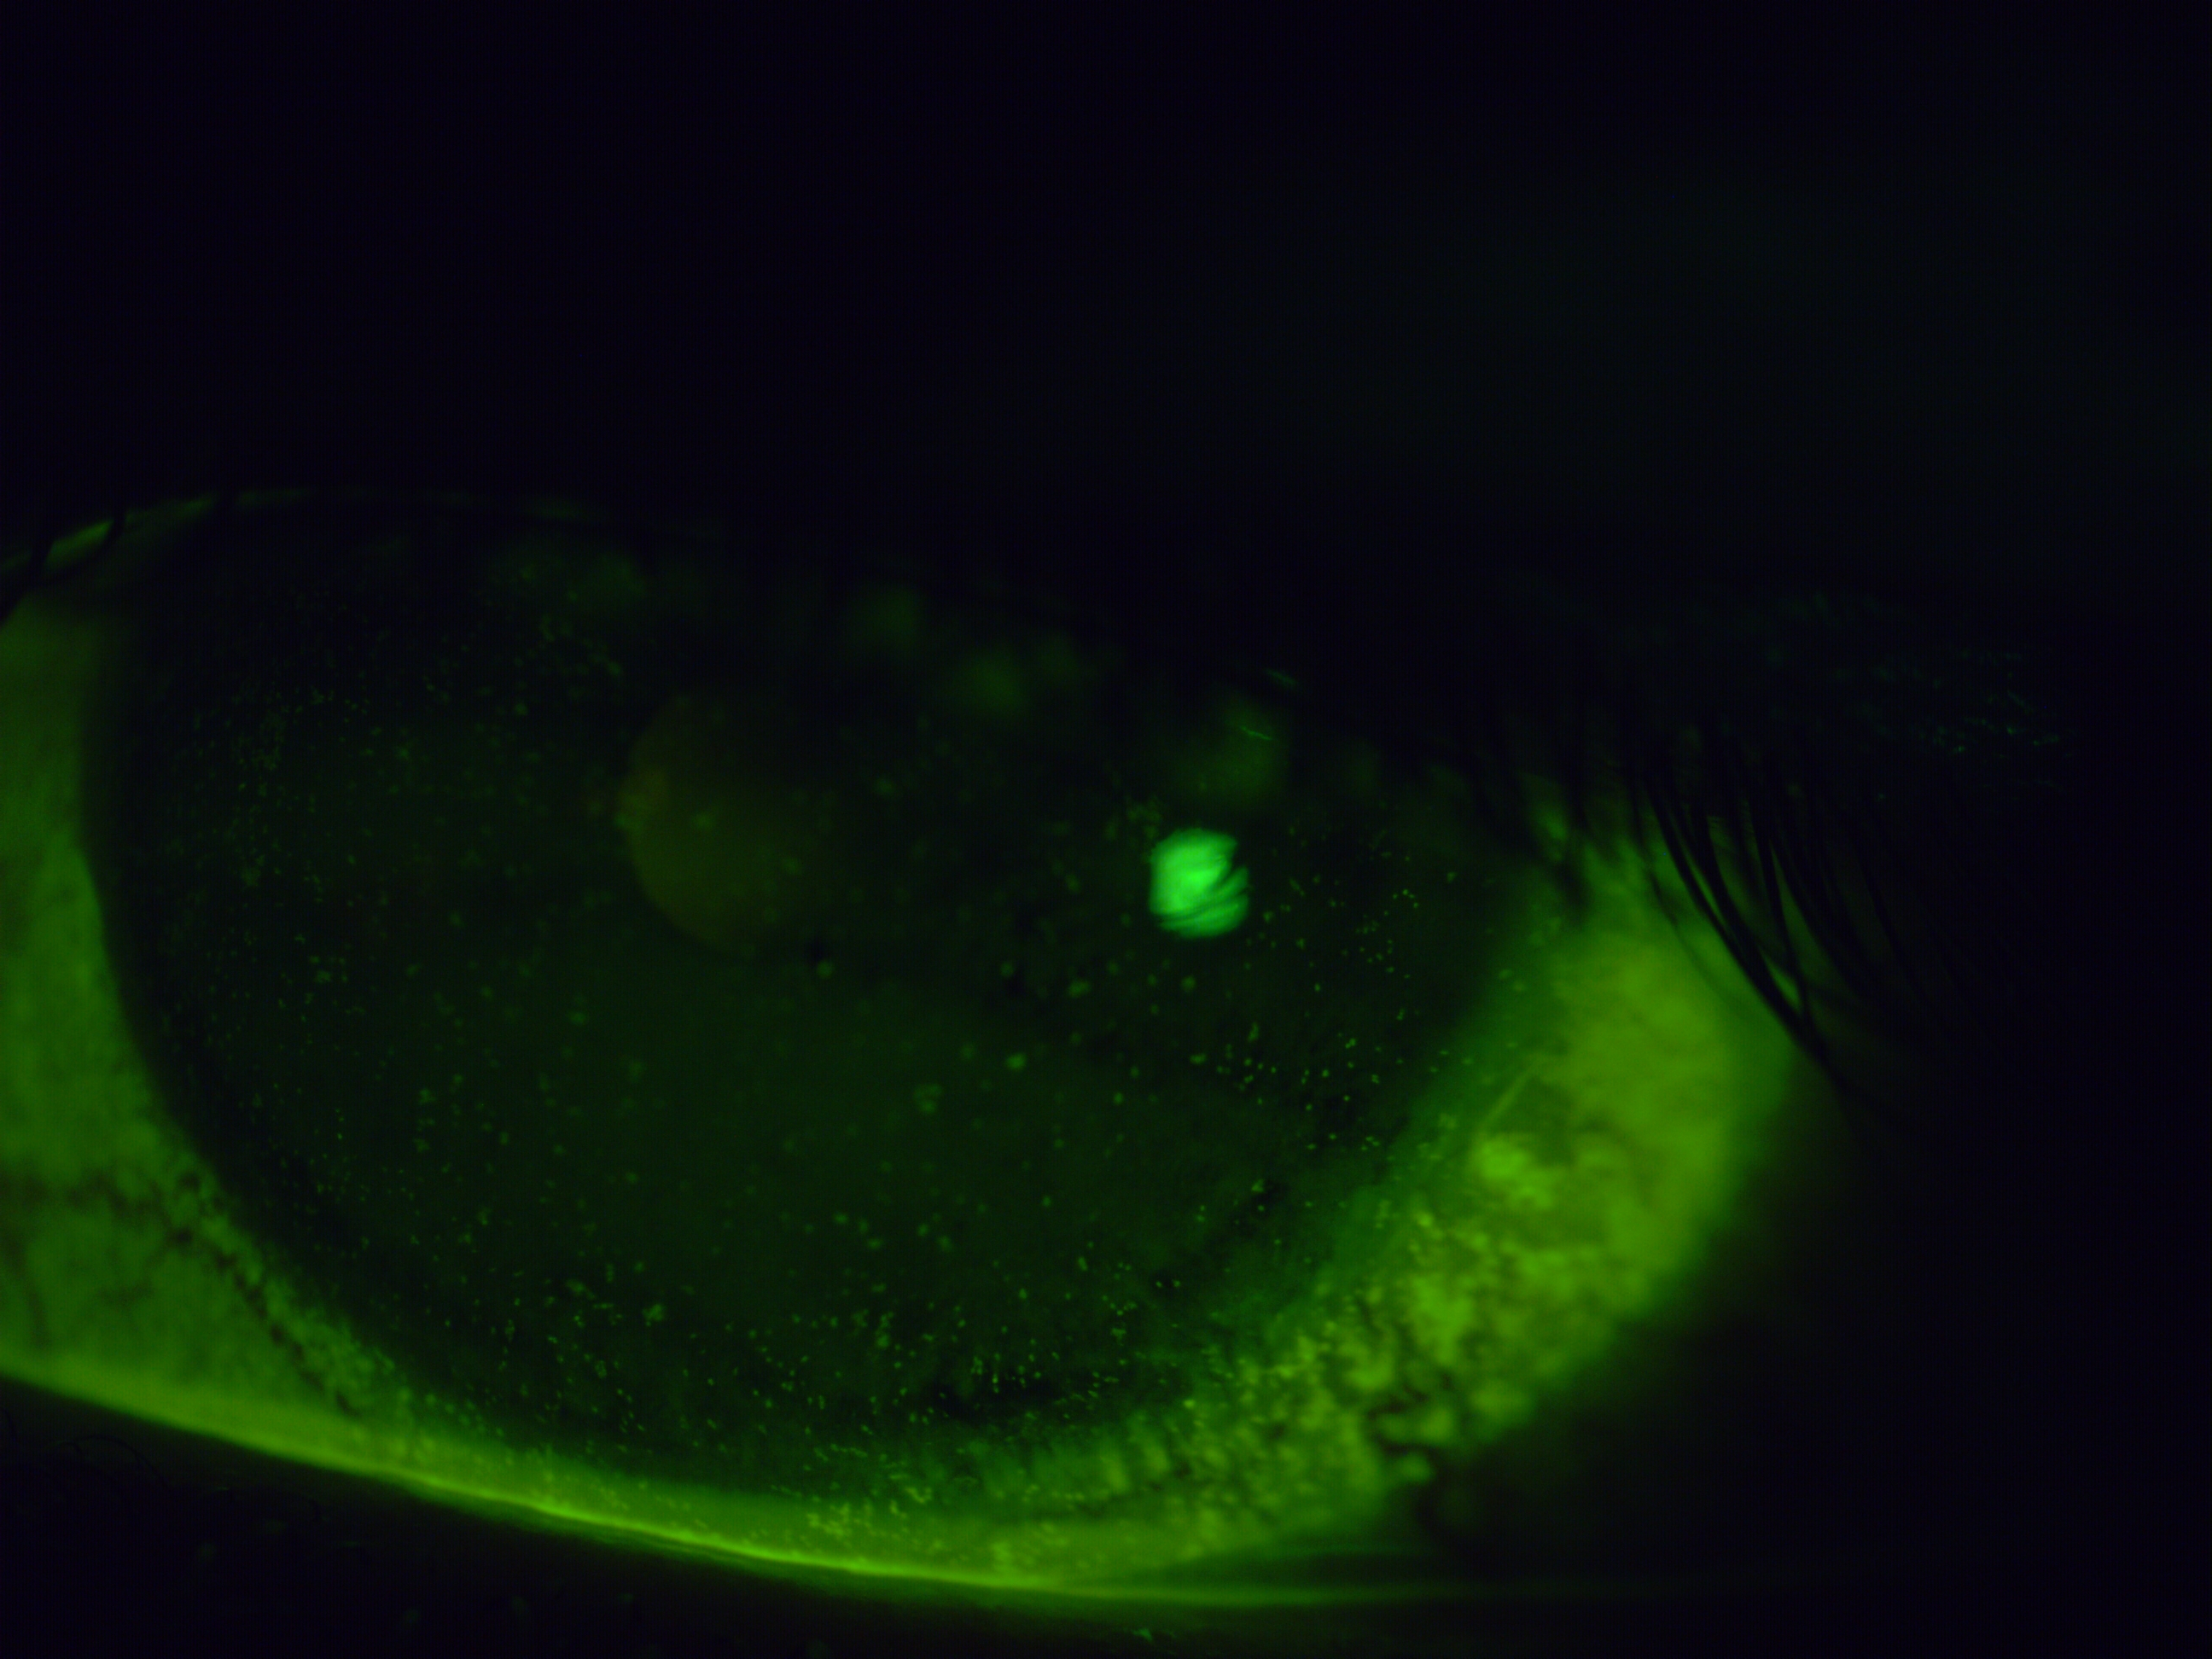

The images below were taken on presentation using fluorescein dye under cobalt blue light — damaged areas of the eye's surface absorb the dye and fluoresce brightly, showing the extent of the problem directly.

The improvement to the surface integrity is visible directly in the fluorescein image taken one week after removal — and reflected in the patient's symptoms. The chronic redness, the surface staining, and the subjective discomfort all showed meaningful improvement, with further gradual recovery continuing in the weeks that followed.